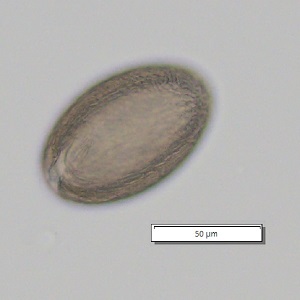

DPDx is an educational resource designed for health professionals and laboratory scientists. For an overview including prevention, control, and treatment visit www.cdc.gov/parasites/.